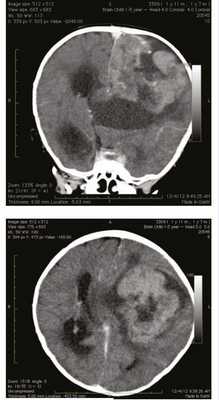

Мальчик в возрасте 1 года 10 мес поступил во II детское отделение ФГБУ «Научно-исследовательский институт нейрохирургии им. акад. Н.Н. Бурденко» с гигантской опухолью левого полушария головного мозга. Ребенок от первой беременности, протекавшей без патологии, первых самостоятельных родов на 37-й неделе. Масса тела при рождении 2750 г, рост 49 см. Мальчик развивался с отставанием в моторном развитии: начал переворачиваться в 6 мес, ползать и сидеть в 7 мес, ходить в 1 год 1 мес. Заболел в возрасте 1 года 7 мес, когда на фоне подъема температуры до 38 °С стал прихрамывать на правую ногу. Проведенная компьютерная томография (рис. 1)

Рисунок 1. Компьютерная томография гигантской опухоли левого полушария головного мозга. выявила гигантскую опухоль левого полушария головного мозга. Также за прошедшие 3 мес отмечен активный прирост окружности головы. В клинической картине заболевания доминировали симптомы внутричерепной гипертензии в виде прогрессирующей макрокрании (окружность головы 60 см), на глазном дне были выявлены признаки внутричерепной гипертензии с развитием атрофии зрительных нервов и слепоты. Также обращала на себя внимание очаговая симптоматика преимущественного поражения левого полушария: ограничение взора влево, центральный парез VII нерва справа, тетрапарез до 4 баллов слева и до 3 баллов справа, рефлексы D>S, диссоциация по оси тела и координаторные расстройства с развитием выраженной атаксии, при этом движения в конечностях были сохранены в полном объеме. Мальчику было проведено тотальное удаление гигантской опухоли, имеющей достаточно хорошую псевдограницу с веществом мозга. После гистологической верификации опухоли ребенок и его родители были консультированы онкологом: было рекомендовано проведение высокодозной химиотерапии. Через 3 мес после постановки диагноза ребенок умер от прогрессии заболевания.